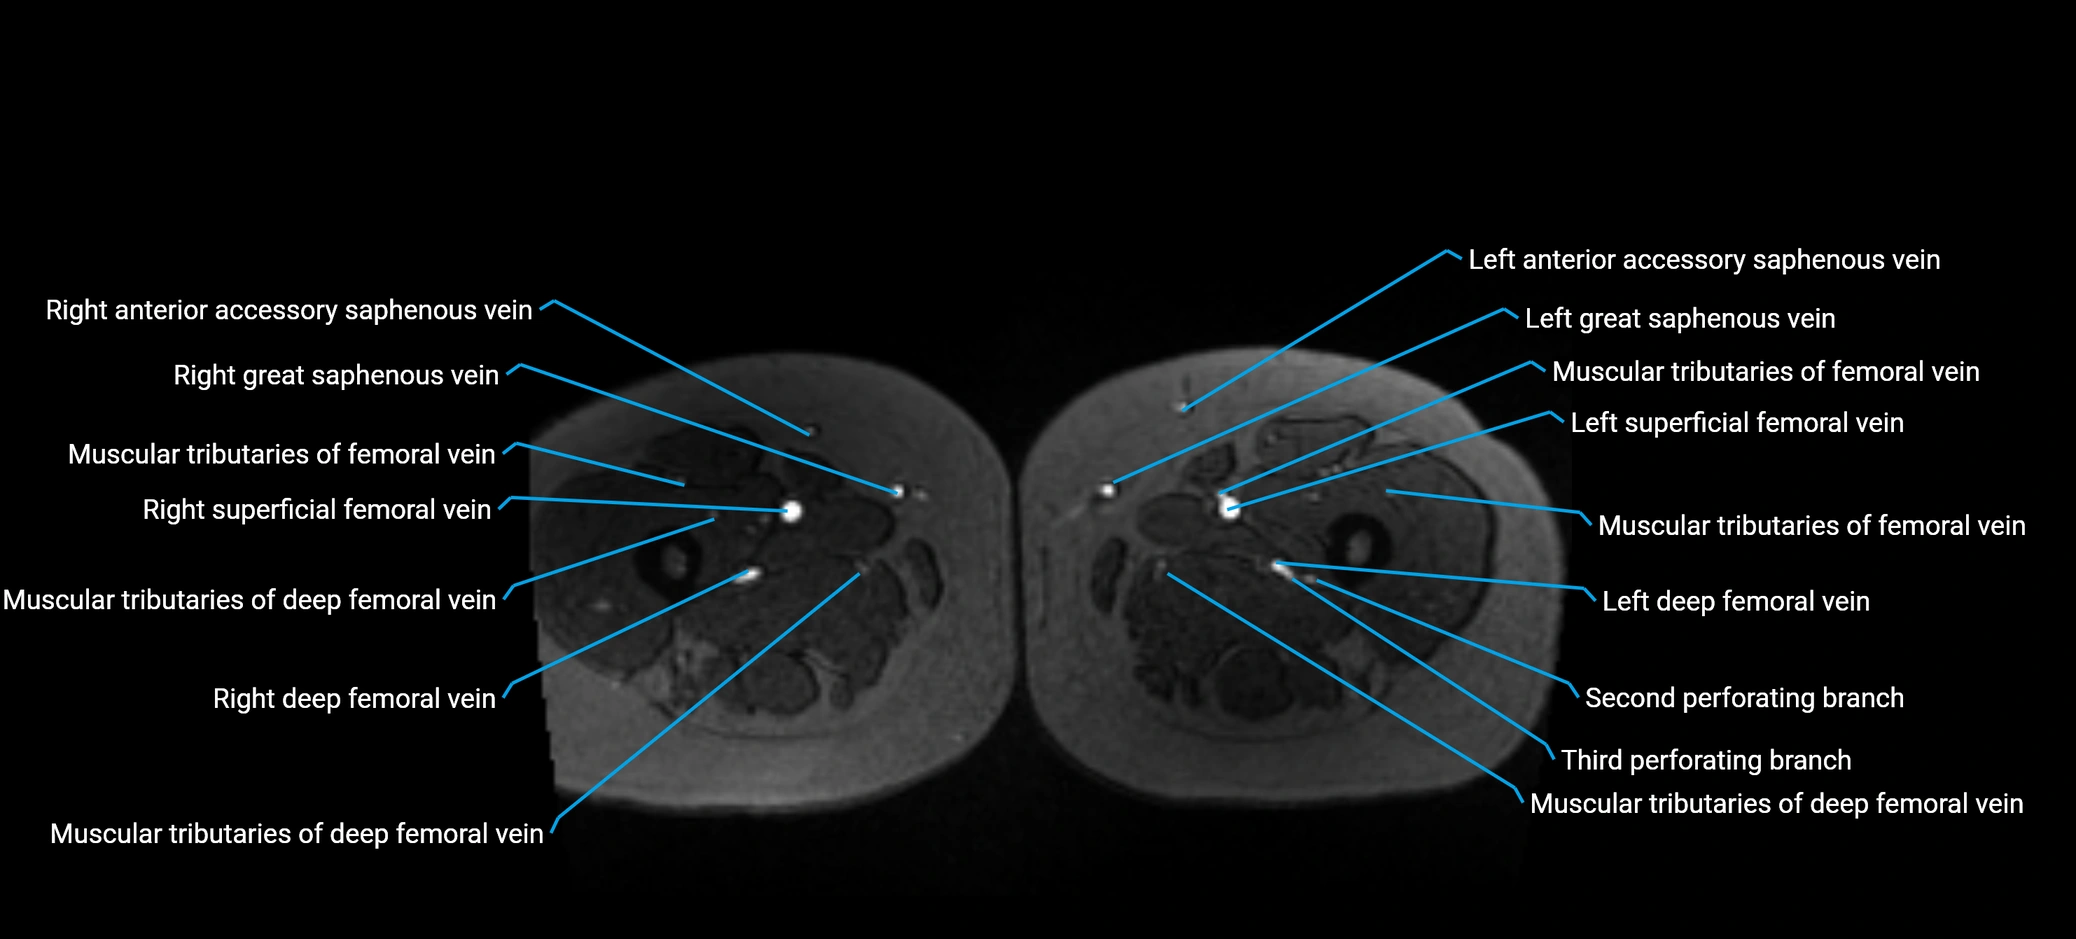

MRI image

image